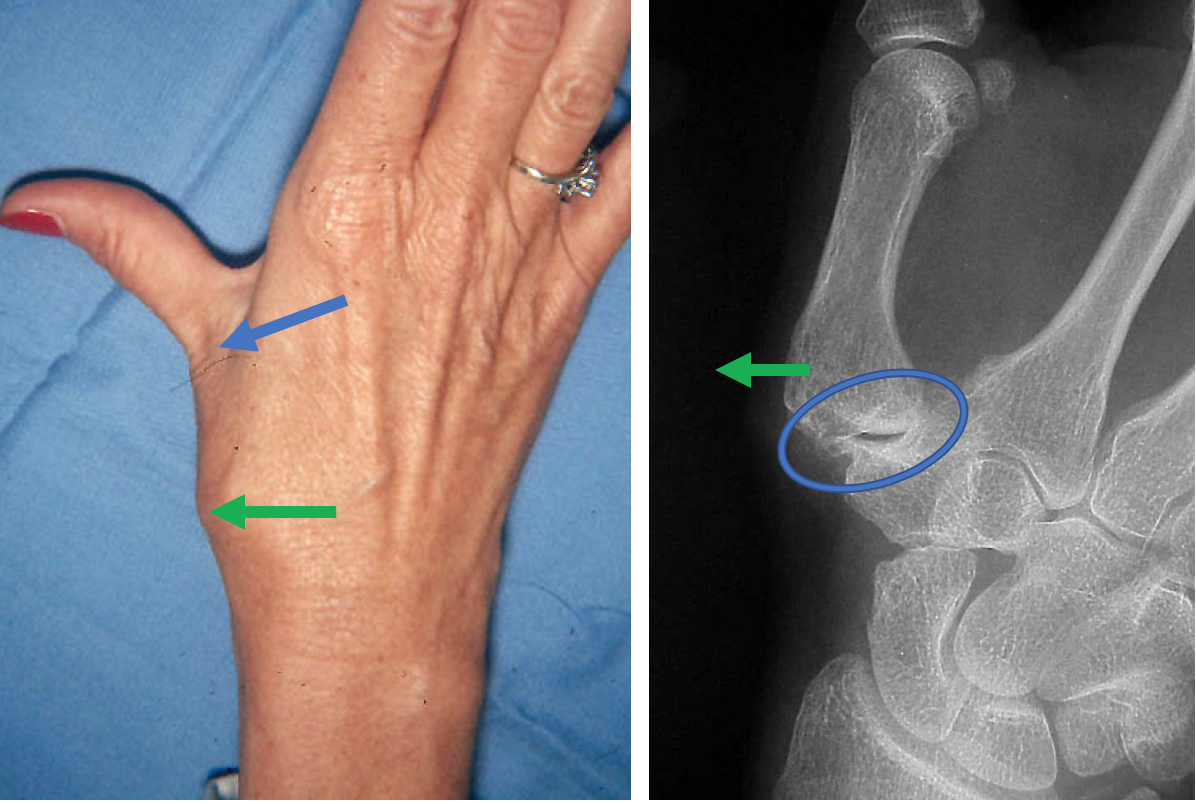

Tendon Suspension Arthoplasty Thomas R. Hunt III, M.D., D.Sc. What Is A Suspension Arthroplasty Web abductor pollicis longus suspensionplasty is a simple, effective treatment alternative forbasal joint arthritis. Web carpometacarpal joint arthroplasty is a surgical procedure in which the trapezium, one of the carpal bones of the wrist that. Web a simple reconstructive method for treating advanced arthritis of the thumb carpometacarpal (cmc) joint with suture suspension arthroplasty. Web suture suspension arthroplasty allows early. What Is A Suspension Arthroplasty.